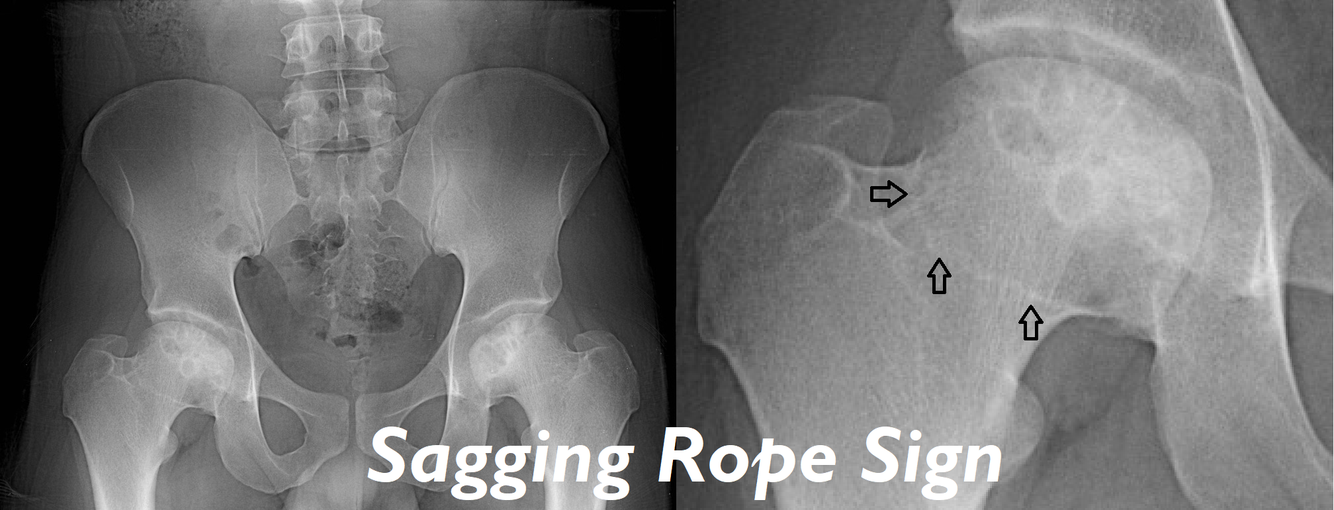

Later cases of AVN show changes on X-ray, what are these changes (before collapse)?

A

1. Patchy sclerosis of the weight bearing area

2. Lytic zone underneath patchy sclerosis (formed from granulation tissue) which causes the classical sagging rope sign (also seen in Perthes)